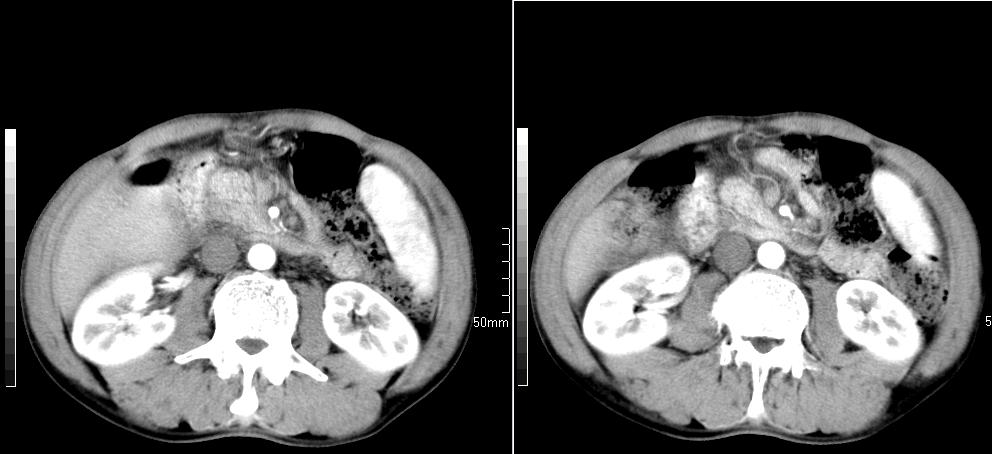

标题: CT26769:男,58岁,腹胀、腹部不适一年余 [打印本页]

标题: CT26769:男,58岁,腹胀、腹部不适一年余

肠系膜脂膜炎,胆囊炎,脾大。建议结合临床。鉴别:慢性胰腺炎并假囊肿形成。

1 慢性胰腺炎并假囊肿形成。2 慢性胆囊炎并累及肝边缘!

1)考虑慢性胰腺炎并假性囊肿形成。2) 慢性胆囊炎。3)肝内胆管扩张。

1肝内胆管扩张,性质待定,2慢性胰腺炎胰管扩张,胰腺颈部假囊肿,3肝左叶低密度为小囊肿,4胆囊炎。